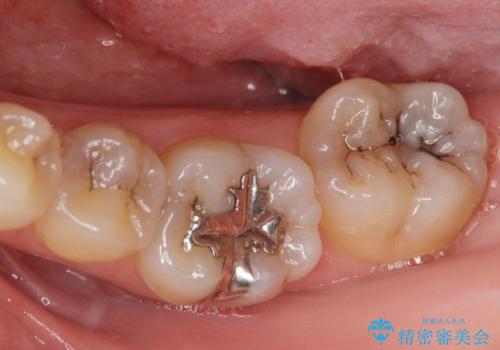

- 前歯の見た目が気になるとの事で来院。

根の治療のやりかえは希望されなかったので土台だけやりかえを行い、ジルコニアクラウンで治療を行いました。